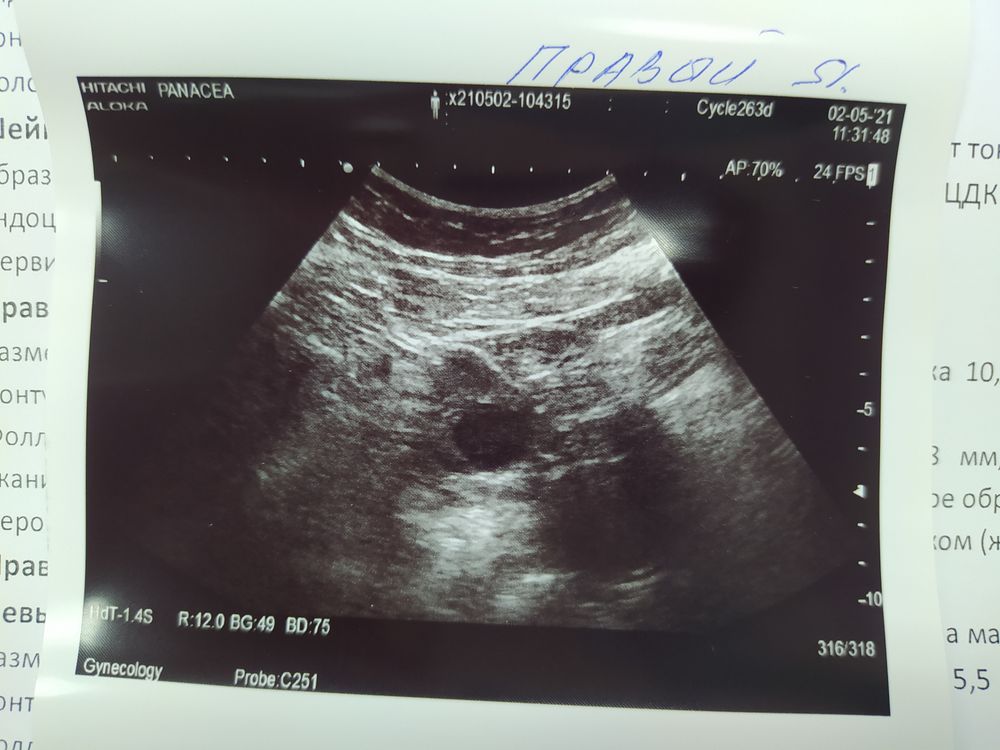

Анализы и процедуры. Помощь в расшифровке результатовГотовлюсь к вступлению в свой первый длинный протокол. Доминантный фолликул разорвался, жидкость на 22 ДЦ в позадиматочном пространстве увидели, на 24 ДЦ (вчера) жёлтое тело в правом яичнике 20мм. Ре написала, что судя по фото (я пока в другом городе), ЖТ полупрозрачное и УЗИ надо повторить ещё раз на 26 дц (свой цикл длинный). А пока сдать прогестерон. Сдала утром, пришёл сейчас результат 0,6 нг/мл, это 25 дц. На 18 дц он был 0,1 нг/мл, то есть рост и есть, но по сути и нет 🙄 Получается, это не жёлтое тело или что? Два узиста подтвердили, что овуляция была, завтра мне на третье УЗИ, а Ре пишет, что не может быть жёлтого тела и такого прогестерона((((( Ерунда какая-то 😥 Кто что скажет хорошего, девчат? Было у кого-нибудь похожее? Он может ещё вырасти до нормальных наконец значений??